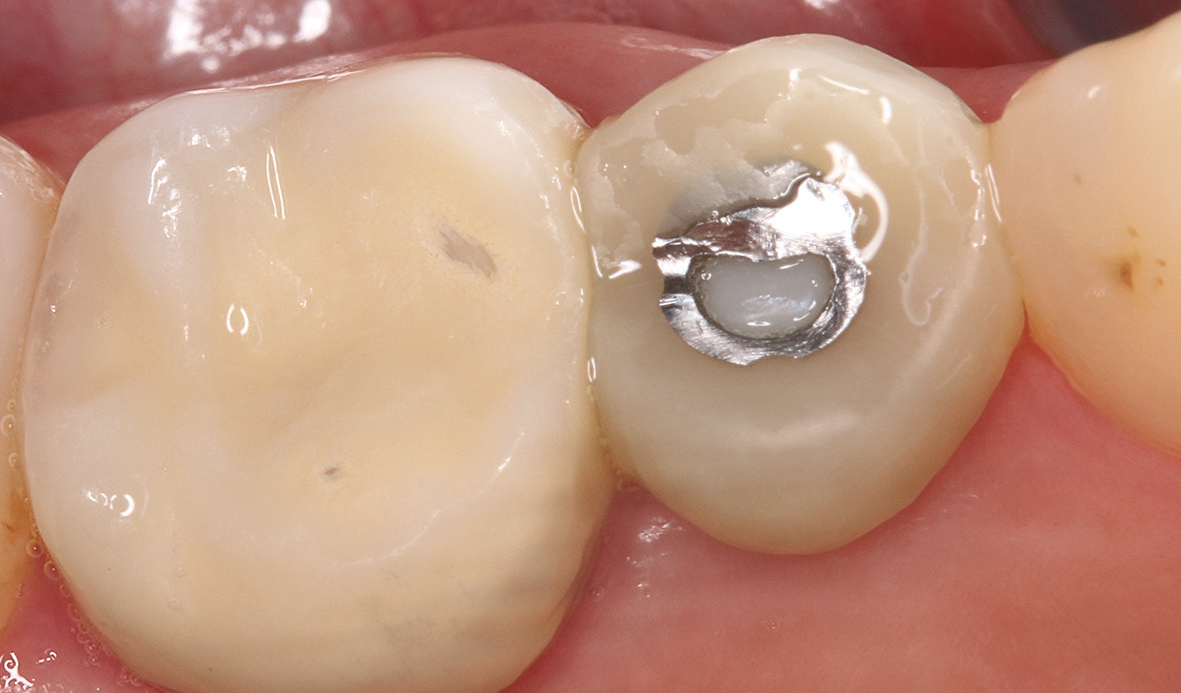

Nach einer komplikationsfreien Einheilzeit von vier Monaten konnte mit der Herstellung des definitiven Zahnersatzes begonnen werden. Hier entschied man sich konsequent für monolithische Kronen aus Lithiumdisilikat, um das Chippingrisiko so gering wie möglich zu halten [12]. Im Zuge der Implantatversorgung wurde nun auch – wie geplant – die metallkeramische Krone an 16 geschlitzt, entfernt und der Stumpf nachpräpariert. Implantatkopf und Zahnstumpf wurden daraufhin zusammen mit A-Silikon analog abgeformt. Für die geschlossene Abformung wurde die Abformkappe (impression.transfer) auf dem Implantatkopf positioniert. Ein deutliches Einrasten signalisierte den lagestabilen Sitz. Für die Modellherstellung rastete das Implantatanalog (lab. replica) ebenso in die integrierte Abformkappe ein. Nach der Herstellung des Meistermodells konnten die beiden Kronen im digitalen Workflow CAD/ CAM-gestützt gefertigt werden. Nach Ausarbeitung, Bemalung und Glasur waren die beiden Kronen für die definitive Zementierung bereit. Die klinische Einprobe der Restaurationen verlief erfolgreich, sodass die Kronen nacheinander mit selbstadhäsivem Befestigungskomposit eingegliedert werden konnten.